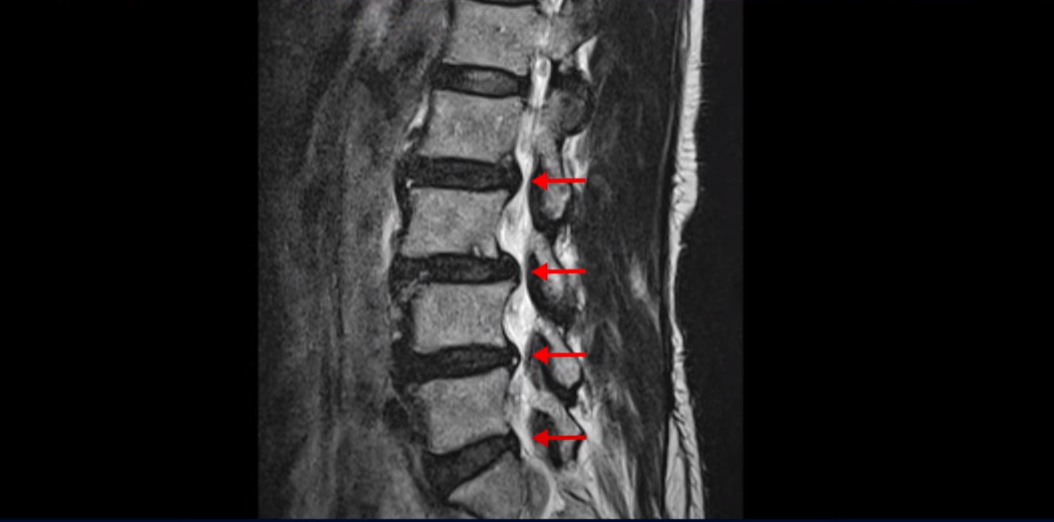

이분 허리를 보면 여러 마디의 퇴행성 디스크와 협착이 있습니다.

2번 3번과 3번 4번은 신경다발이 지나가는 척추관도 좁아져 있습니다.

또 3번 4번에는 척추뼈가 밀려나간 전방전위증도 있습니다.

이분은 정형외과 병원에서 3마디 디스크 파열이라고 수술 권유를 받았는데 저희는 디스크 파열은 잘못된 진단이라고 봅니다. 여러 마디 보이는 디스크 문제는 파열이 아닌 퇴행성디스크들이고 아픈 원인은 전방전위와 협착증 증상입니다. 전방전위와 협착증이긴 하지만 아주 심한 게 아니고 발병한지도 얼마 되지 않아서 근육재활치료를 하면 2주 정도면 빨리 호전될 수 있는 상태였습니다. 왜 이런 환자가 치료하기 훨씬 쉬운 건지, 치료는 어떻게 하는 건지 지금부터 설명 드립니다.